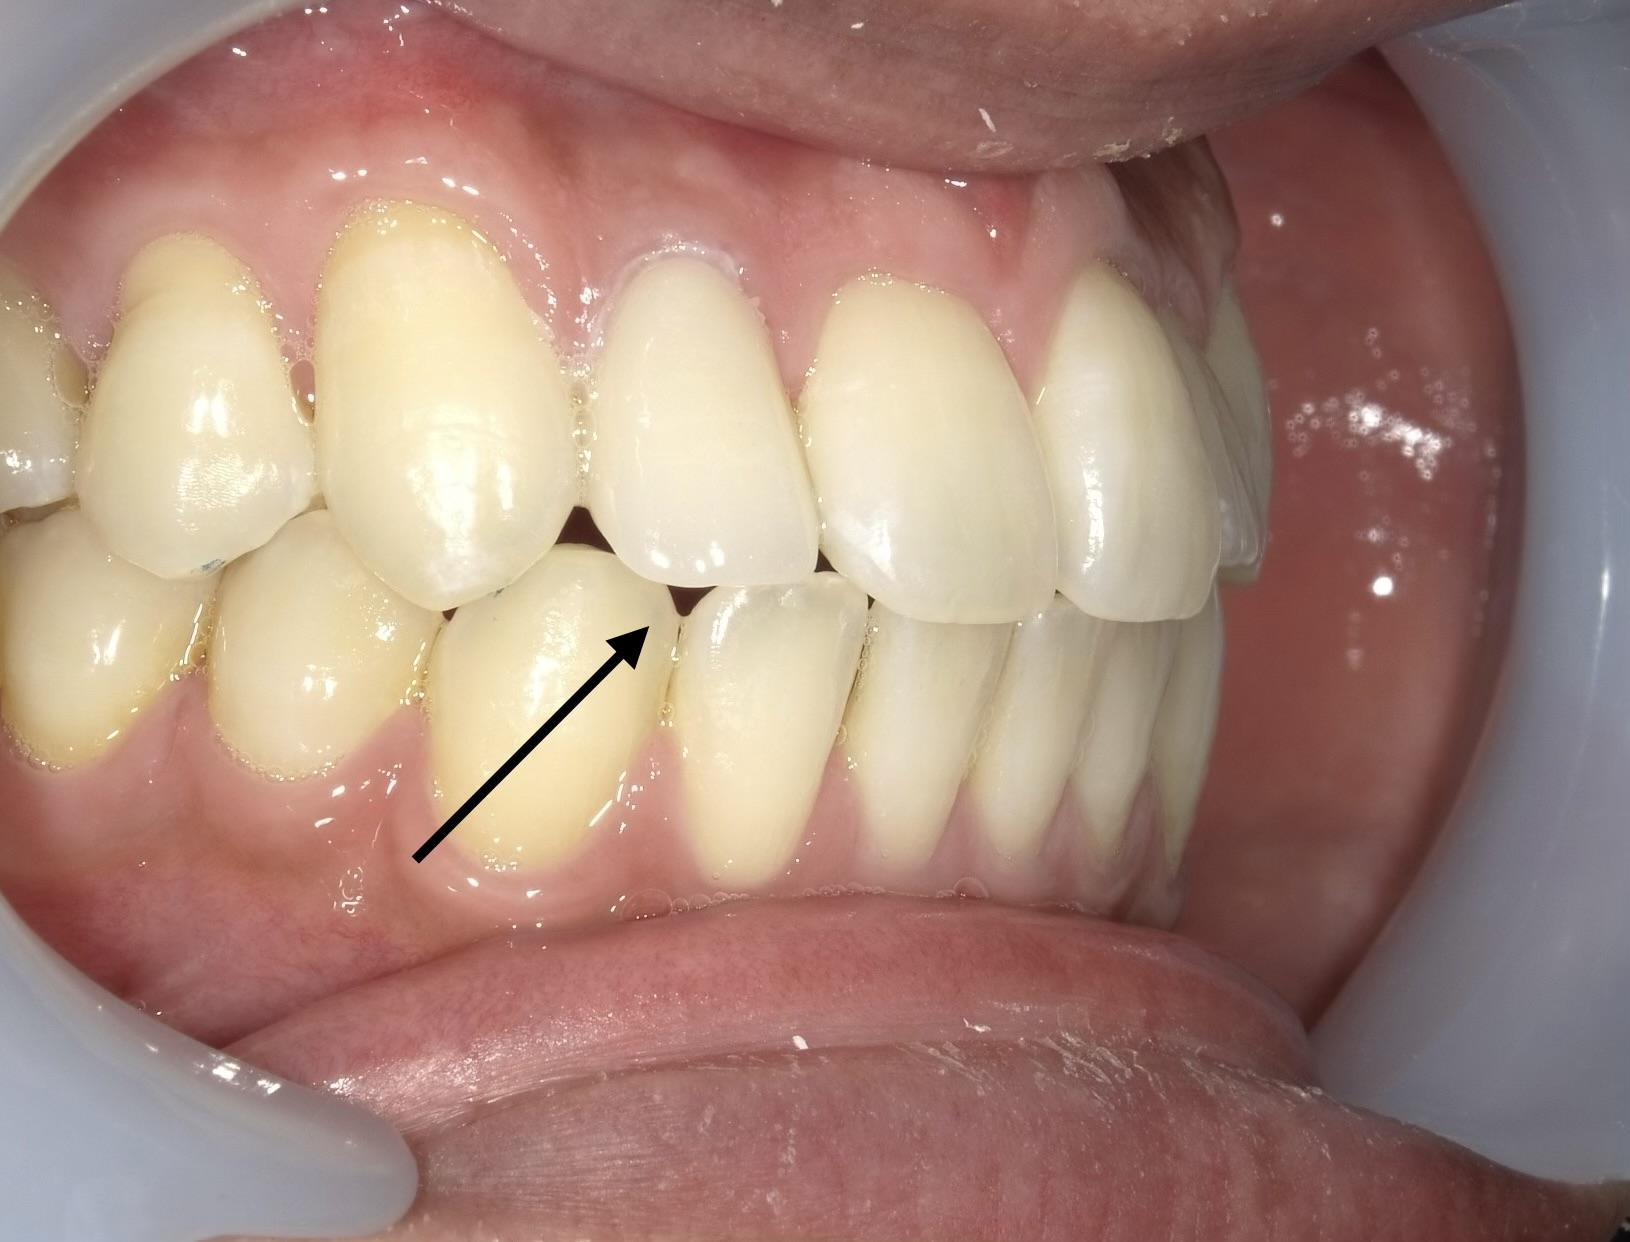

症例2:変色と形のアンバランスを同時に解消

変色に加え、歯の形も整えたいというご要望。2本のセラミッククラウンを用いてバランスを整えました。隣の歯の変色した詰め物は範囲が小さいためダイレクトボンディング法で詰め直しが可能です。

- 治療方法:セラミッククラウン(2本) + ダイレクトボンディング

- 治療期間:約2ヶ月 / 費用:¥312,400(税込)